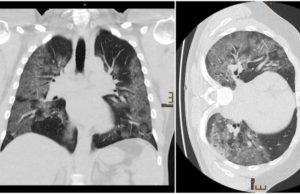

Cum arată radiografia la plămâni a unui medic infectat cu Covid-19

Medic infectat cu Covid-19Radiografia arată răspândirea virusului

Clinica respectivă este cunoscută pentru reticența de a pune imediat pacienții cu dificultăți de respirație pe ventilatoarele mecanice,...